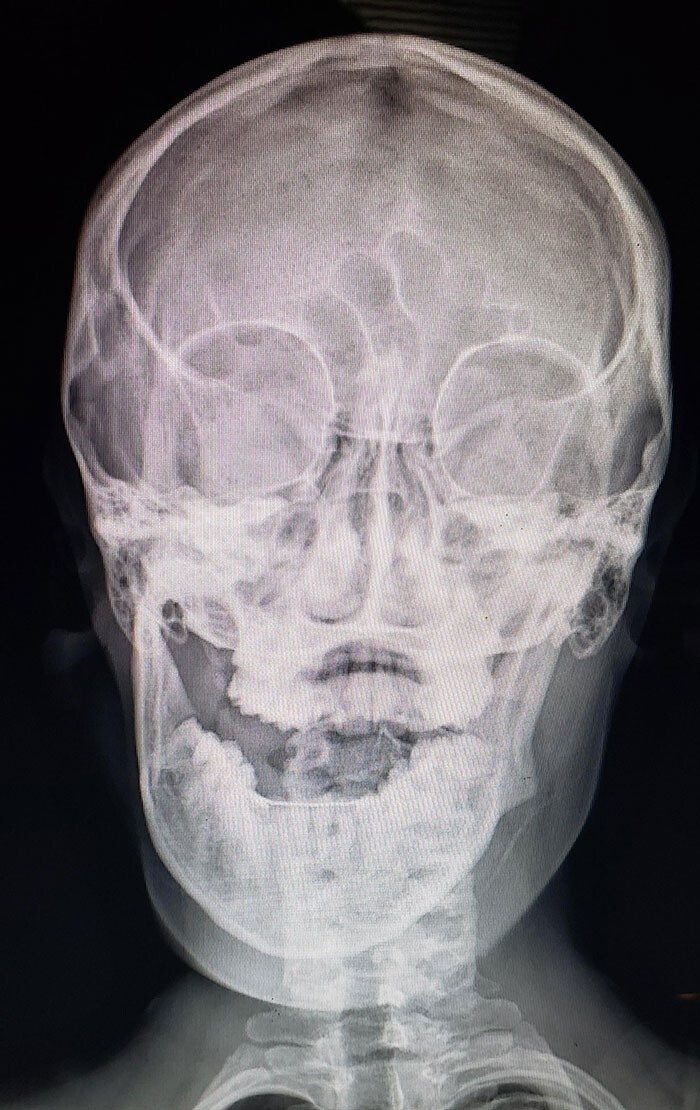

«Ел мюсли. Вывихнул челюсть»